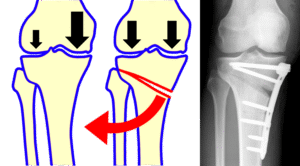

Остеотомия: введение в мир челюстной хирургии

Остеотомия — это высокотехнологичная хирургическая процедура, призванная исправить деформации челюстей и улучшить функцию и эстетику лица. Применяемая как в стоматологии, так и в челюстной хирургии, остеотомия играет ключевую роль в восстановлении здоровья пациента и его уверенности в собственном внешнем виде. В нашей статье мы рассмотрим, что именно включает в себя остеотомия, как проходит процедура, кому …